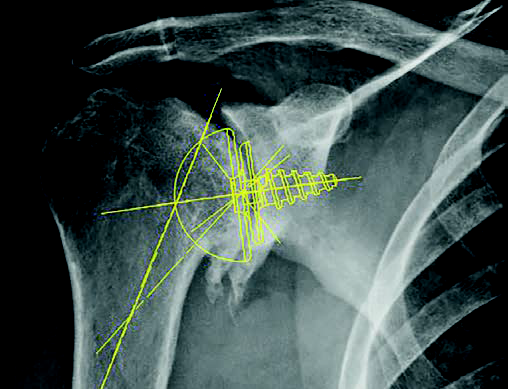

This is completely inexplicable to me because the scale distortions in the shoulder area are immense in X-ray images on transparencies. Because of the images

the different body postures during the X-ray exposures, the

the X-ray images, the resulting considerable size deviations due to the distance to the X-ray film, and the resulting lack of accurate representation of the

bones in the required standard planes, precise size and angle measurement is practically impossible.

is practically impossible. In addition, we now live in

an ever-increasing digital world, planning with normal one-dimensional X-ray images is no longer up to date!

A modern orthopedist no longer has X-ray images on slides. I explain to the patient his arthritis changes in the digital X-ray. In case of significant bony defects, I measure them directly in the digital image via

DICOM calibration with the character measurement program and explain to the patient in the X-ray or better in the

cross-sectional MRI or CT, these wear-related changes, including the corresponding consequences. In the case of a planning system connected to the PACS, the implant can also be shown at the same time and, if necessary